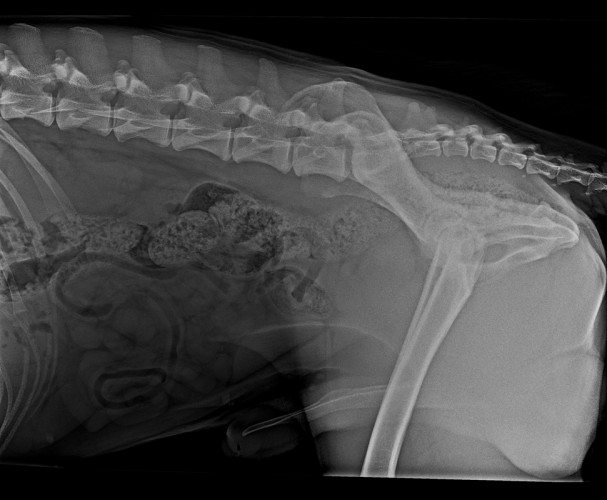

Wir warten jetzt mal die offizielle Auswertung ab. Bin auch gespannt, was nun bei OCD und Lendenübergangswirbel rauskommt. Und welcher LÜW-Typ.

Blackie nach dem Drama mit Ero habe ich mir geschworen niewieder Röntgenbilder zu kommentieren, habe aber gelernt, dass es sich lohnt zuversichtlich zu sein

Das ist ganz einfach. Man schreibt ne Email, bittet um ein Privatgutachten und schickt ihm die Röntgenbilder.

Das Ergebnis + Rechnung kommt echt schnell ( 1-2 Tage)

Ich habe das Vorgutachten anfertigen lassen, weil ich die Nerven verloren habe und ich dachte der Hund hat was gröberes (ED mittel oder schwer).

Ich hatte das Gutachten in Auftrag gegeben, bevor die Bilder offiziell eingeschickt wurden, um zu entscheiden ob ich die Bilder überhaupt noch einschicke (Kosten Vorgutachten: 60€, Kosten offiziell einschicken & eintragen in Österreich: 200€).

Da ich Ero's Bilder nun ja doch offiziell eingeschickt habe, darf ich dann auch 260€ löhnen ![]()

In deinem Fall würde ich mir das Geld für das Gutachten sparen. Die Prognose ist gut und die Bilder sind schon weg.

Es seidenn es ist dir 60€ wert, dass du das Ergebnis vorher schon hast. Aber bindend ist dieses Ergebnis ja auch nicht.

Ich bin bezüglich Ero nun zwar erleichtert, aber "Amen" sag' ich erst, wenn bei der offiziellen Befundung dieselben guten Ergebnisse rausgekommen sind. ![]()